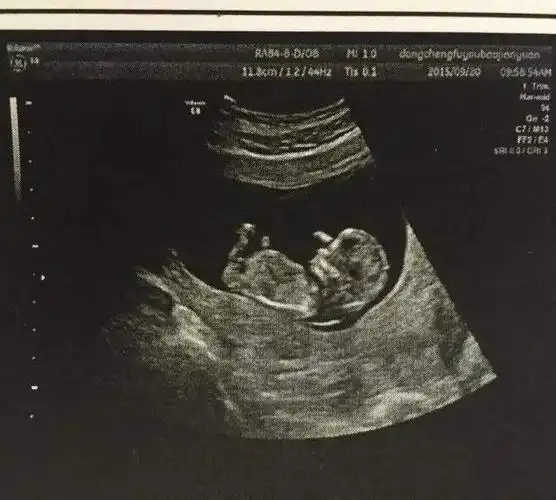

孕期b超做多了对胎儿不好只要在这个时间范围内都安全